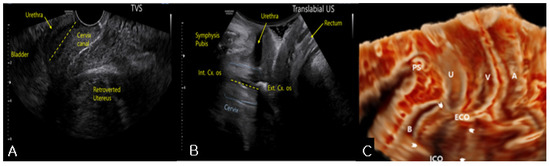

We performed a robot-assisted laparoscopic total hysterectomy with a left salpingo-oophorectomy. Endometriosis and adhesion bands were noted on the surface of the left ovary and fallopian tube (Figure 3B), but no adhesions were noted between the uterus and the bladder (Figure 3C). Hence, it was not an adhesion-related issue; rather, it resulted from the action of the lever principle. The patient urinated normally immediately after the removal of the urethral Foley catheter 2 days after the operation. The patient maintained normal urination at the 1- and 48-month follow-up visits.

Figure 3. Robot-assisted laparoscopic view. (A) The fibroid Ut and both adnexae without adhesion between the anterior peritoneum and the uterus were noted; (B) The LT and LO were adhered together, and endometriosis spots and filmy adhesions were noted on the surface of the LO. There were no adhesions between the uterus and the posterior peritoneum; (C) Dissecting the bladder peritoneum revealed that there was no dense adhesion between the Bl and the Cx. LT, left fallopian tube; LO, left ovary; RT, right fallopian tube; Cx, uterine cervix; Ut, uterus; Bl, bladder.